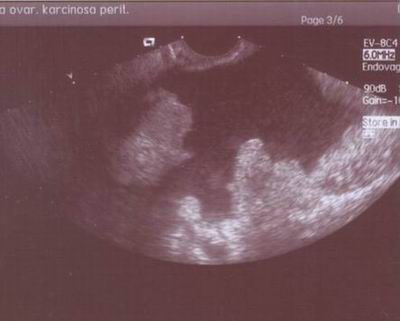

Pokročilá: Ascites, meta omenta a střeva: zvětšení břicha, obstipace, nausea, meteorismus, kachexie

- Zobrazovací metody: US diagnostika Senzitivita: 87 %, specificita: 67 % Ferrazi,1997, grey scale US, Doppler US ( 0.4 RI: 100 % senz. 96-99% spec.), jiné zobrazovací metody (nemá lepší výsledky), MRI, CT, PET…

- Tumor markery (CA 125, Makar 1993: 90% předoperačně, Monoklonální protilátky)